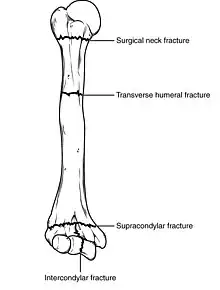

Humerus fracture

Classification

Fractures of the humerus are classified based on the location of the fracture and then by the type of fracture. There are three locations that humerus fractures occur: at the proximal location, which is the top of the humerus near the shoulder, in the middle, which is at the shaft of the humerus, and the distal location, which is the bottom of the humerus near the elbow.[9] Proximal fractures are classified into one of four types of fractures based on the displacement of the greater tubercle, the lesser tubercle, the surgical neck, and the anatomical neck, which are the four parts of the proximal humerus, with fracture displacement being defined as at least one centimeter of separation or an angulation greater than 45 degrees. One-part fractures involve no displacement of any parts of the humerus, two-part fractures have one part displaced relative to the other three; three-part fractures have two displaced fragments, and four-part fractures have all fragments displaced from each other.[13][14][3] Fractures of the humerus shaft are subdivided into transverse fractures, spiral fractures, "butterfly" fractures, which are a combination of transverse and spiral fractures, and pathological fractures, which are fractures caused by medical conditions.[12] Distal fractures are split between supracondylar fractures, which are transverse fractures above the two condyles at the bottom of the humerus, and intercondylar fractures, which involve a T- or Y-shaped fracture that splits the condyles.[7]